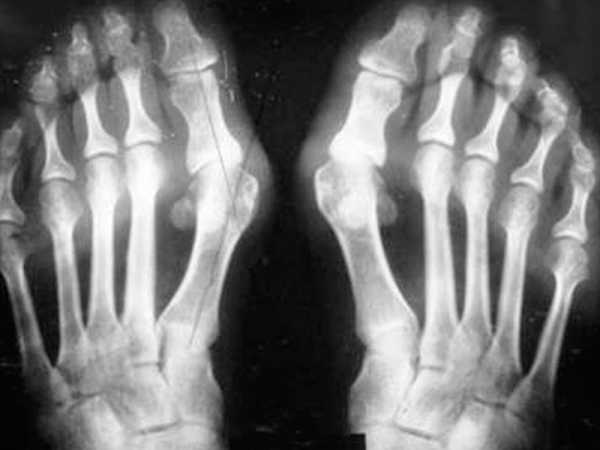

Ревматоидный артрит является аутоиммунным заболеванием, которое не уступает по своей распространенности подагре. Иммунитет человека по какой-то причине начинает отвергать собственные клетки организма, атакуя их, воспаление развивается как следствие этого механизма. Ревматоидный артрит носит системный характер и поражает одновременно несколько суставов. В процессе развития заболевания появляется выраженная деформация, а визуально участки искажены.

Среди отличительных симптомов можно выделить симметричность процесса. Поражаются одновременно одни и те же суставы обеих конечностей, например, оба колена, голеностопа и т. д. Пациенты отмечают утреннюю скованность в подверженных заболеванию частях, предварительно им необходимо выполнить разминку или даже самомассаж. В отличие от других поражений суставов, при ревматоидном артрите пациент чувствует облегчение только во второй половине дня. Наряду с локальными изменениями, больные отмечают общую утомляемость, слабость, потерю веса, снижение аппетита и дискомфорт в окружающих мышцах, вплоть до болевых ощущений.

Симметричность процесса при ревматоидном артрите